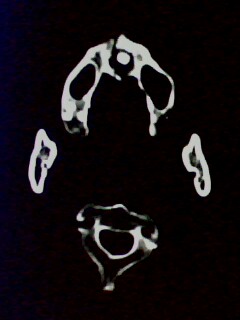

以下是引用随光逐影在2009-5-20 19:22:00的发言:[br]1)考虑左上颌骨近中线区含牙囊肿。2)鼻中隔右突偏曲。3)双侧下鼻甲肥大。

以下是引用余辉在2009-5-20 19:35:00的发言:[br]1)考虑左上颌骨近中线区含牙囊肿。2)鼻中隔右突偏曲。3)双侧下鼻甲肥大。[br]支持,不除外上颌骨正中囊肿,有窦道通鼻前庭,出血可能是内部有感染,图像不是很清,可照个片看一下